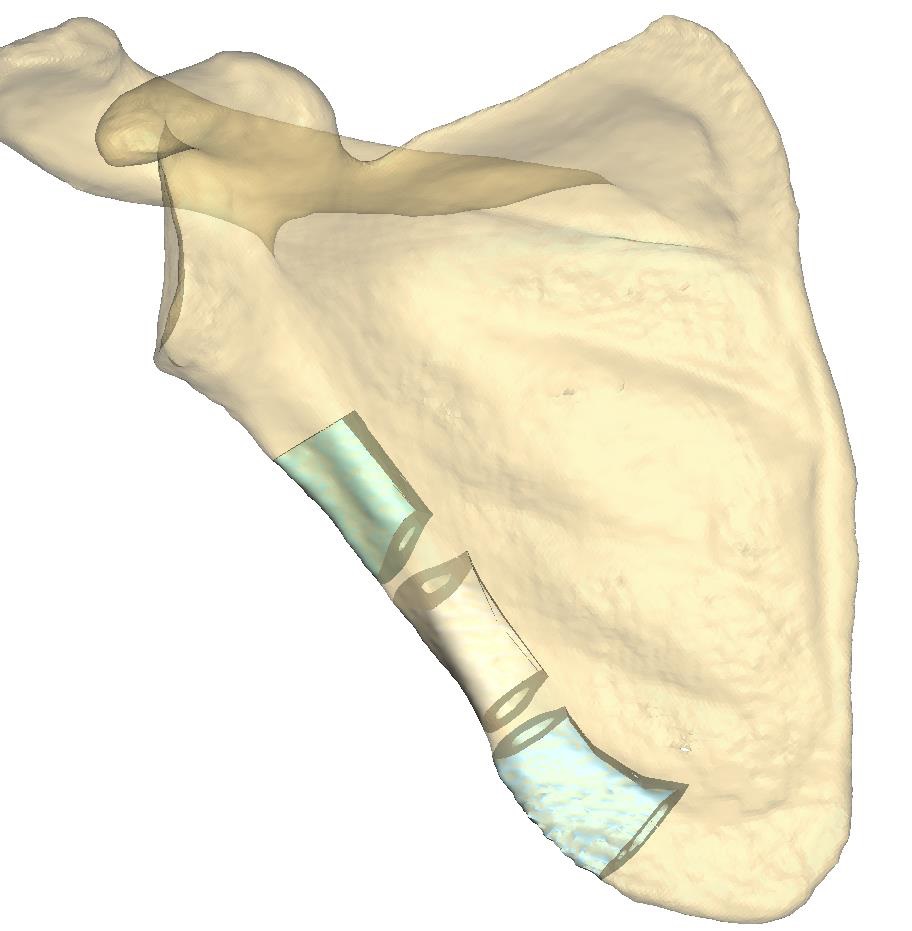

Computer-assisted planning (ProPlan CMF/TRUMATCH CMF Solutions) provides a virtual 3 dimensional model for a detailed osseous reconstruction of the maxilla or mandible with sub-segments of the lateral scapular border and/or tip (Fig. 1) based on high-resolution CT scans of the craniofacial skeleton and scapular region. To transfer such graphical representation accurately into real surgery requires an assorted toolkit of stereolithography (STL) models, selective laser sintered (SLS) templates for bone contouring and sub-segmentation osteotomies and patient specific implants (PSI).

The specific anatomic conditions along the lateral scapular border led to the development of biplanar cutting guides consisting of a frame component and a vertical rod rider used in a plug on mode. (Fig. 2) The framework makes up a template which marks the outer margins of the in toto bone segment to be delivered in a first step (Fig. 2). It rests on two footplates at the cranial and caudal ends. Each of these footplates holds a connector socket to accommodate a removable vertical rod rider spanning the entire vertical length of the bone flap. The framework component is applied to the posterior bone surface after a rectangular channel has been opened through the infraspinatus muscle (Fig 2c). The bone flap segment is not cut out along its final borderlines initially. It remains affixed to the footplates until the wedge ostectomies have been performed, allowing its division into further sub-segments (Fig. 2c and 3). For this purpose, the rod rider component of the cutting guide equipped with two hovering pairs of slots and flanges is plugged on. It is convenient to continue the sub-segmentation on a side table, after ligation of the entire flap (Fig. 6, in Clinical Case section).